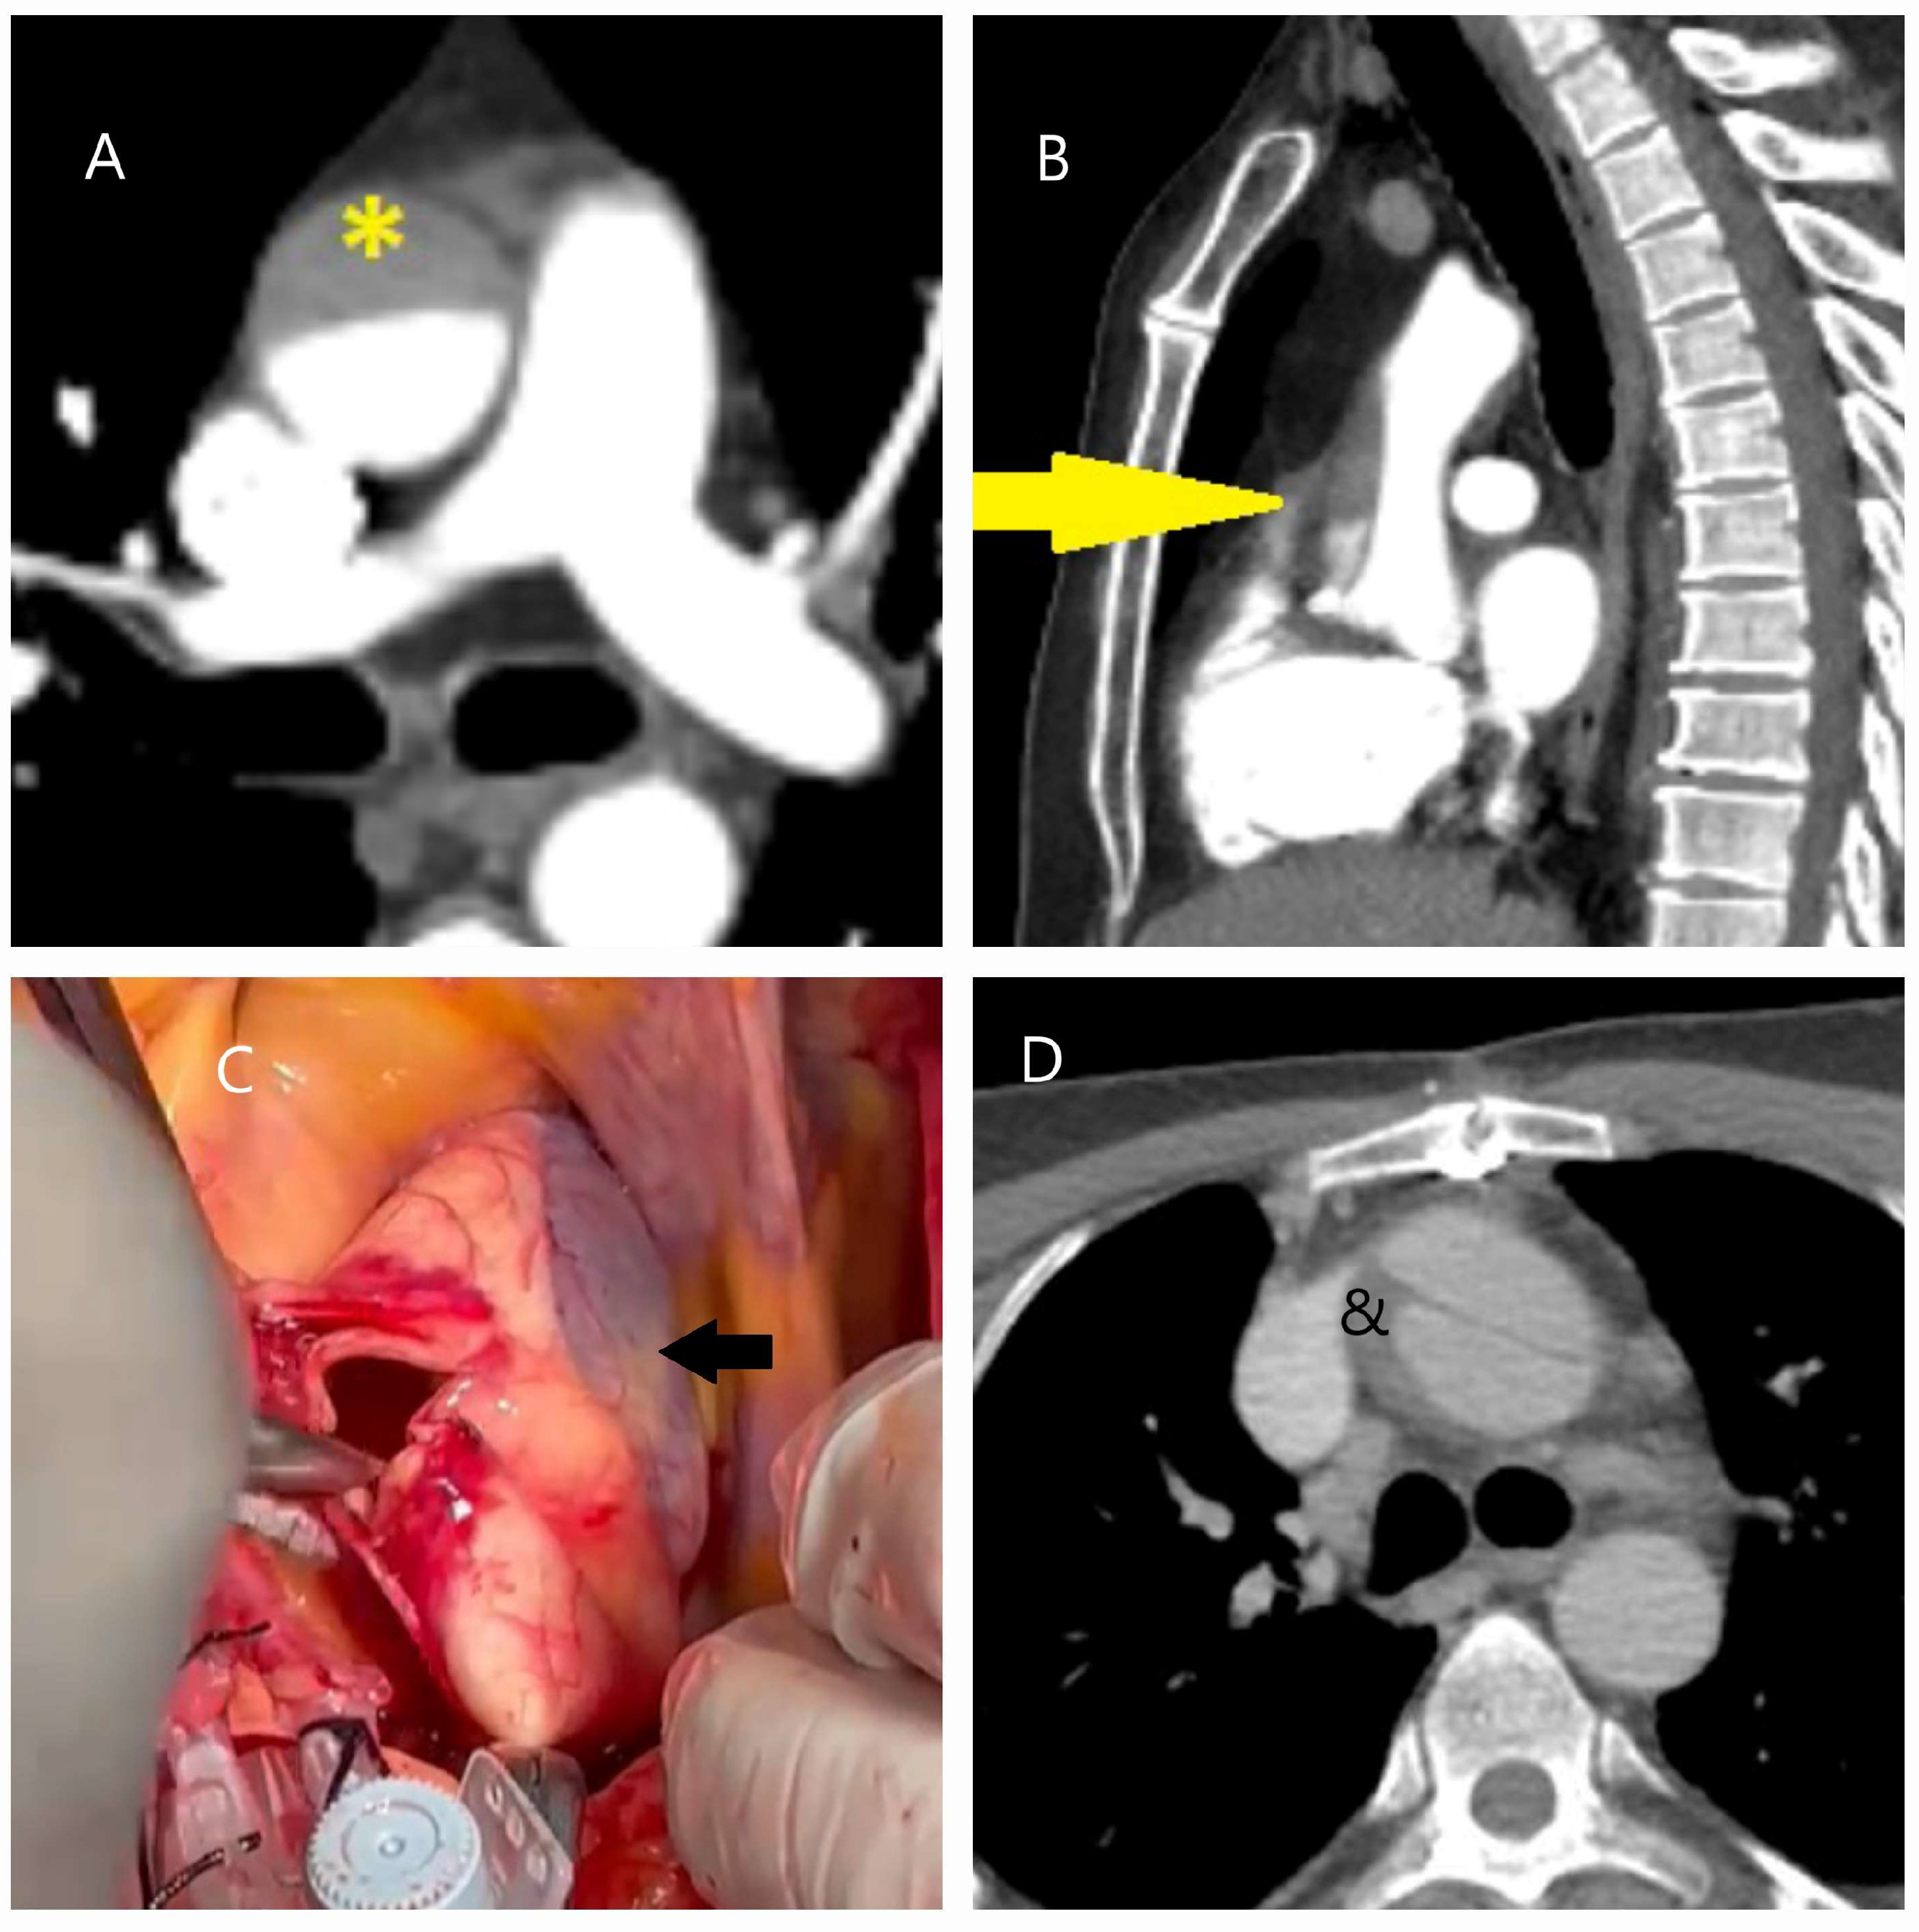

4.1. Dissection, Intramural Hematoma, and Penetrating Aortic Ulcer